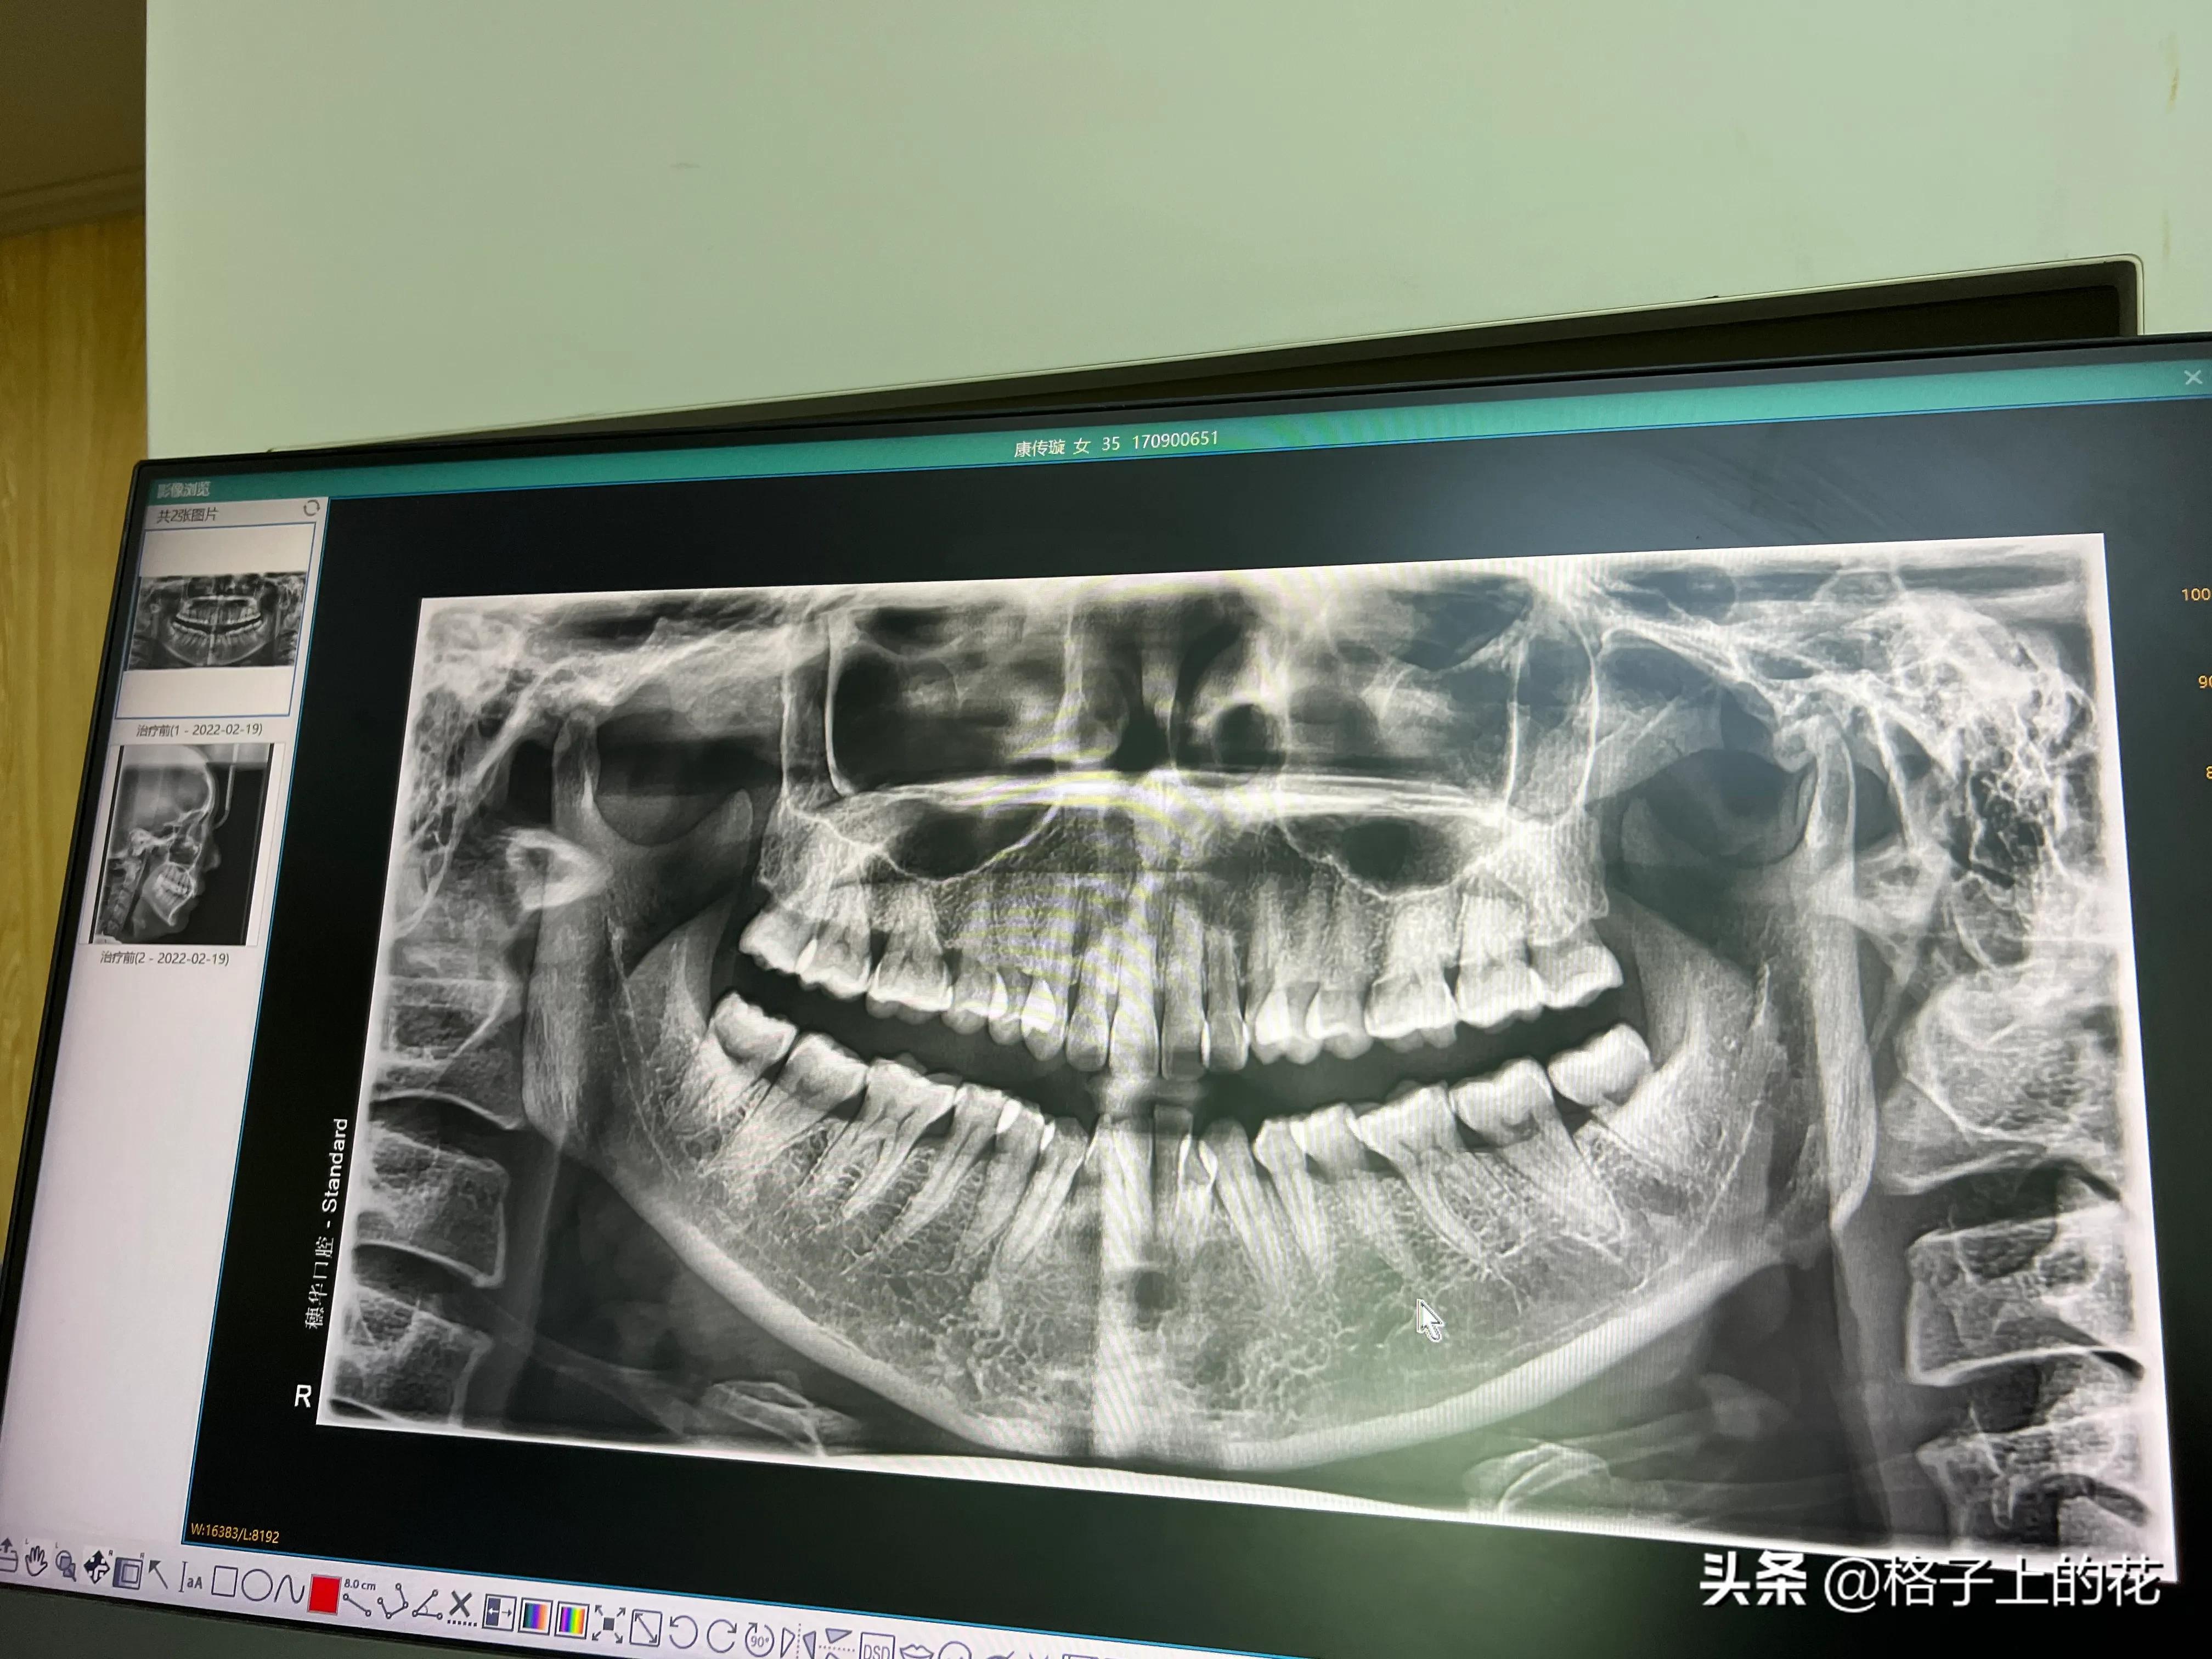

医生是个年轻的女生,说话温柔,态度和蔼。她打开电脑,给我看X光片给我讲解我的牙齿问题。好家伙,科技发达的医生从头到尾没让我张开嘴,看我的牙齿。

X片

过了个星期,周末我再次去到医院。医生拿着专业的X光片、我的3D牙齿动画,还有一个我叫不出来的牙齿骨骼数据图,给我专业认真的分析我的问题。好在,我不属于骨性,不需要额外的治疗。